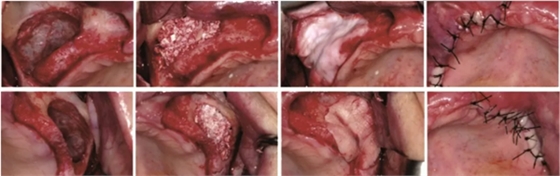

1、CGF/PRF作為屏障膜使用

在引導(dǎo)骨再生術(shù)中,需要使用可吸收或不可吸收的屏障膜,為骨組織的再生提供不受干擾的空間。如果使用CGF/PRF作為屏障膜,其相對目前臨床使用的可吸收生物膜是否具有優(yōu)勢?Gassling等進(jìn)行了一項(xiàng)臨床研究[4],研究納入了6例需要進(jìn)行雙側(cè)上頜竇外提升的患者,在完成植入骨替代材料后,一側(cè)使用PRF壓制而成的屏障膜覆蓋開窗處,而另一側(cè)則使用目前臨床廣泛使用的Bio-Gide生物膜覆蓋,如圖1示,以對比兩者的差異。作者發(fā)現(xiàn),術(shù)后患者兩側(cè)水腫、疼痛及初期創(chuàng)口愈合情況無明顯差異,術(shù)后5個月行種植體植入術(shù)時,作者同時取出部分骨組織行組織學(xué)評估,發(fā)現(xiàn)兩組在新生骨的比例和骨替代材料的剩余比例上均無差異。

學(xué)者研究發(fā)現(xiàn),單獨(dú)使用CGF/PRF作為屏障膜,因?yàn)槠浣到馑俣容^快,無法達(dá)到理想的屏障效果。當(dāng)聯(lián)合生物膠原膜使用時,未見明顯的促進(jìn)成骨效果,同時增加了手術(shù)費(fèi)用和手術(shù)難度。亦有學(xué)者表示CGF/PRF作為膜使用,聯(lián)合生物膠原膜應(yīng)用于GBR植骨術(shù)中時,可以促進(jìn)局部軟組織的愈合,降低感染的幾率。